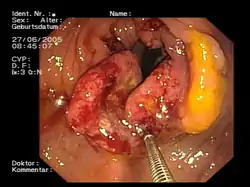

Billede taget ved en kikkertundersøgelse af tyktarmen. Der kan ses en stor svulst, der næsten fylder hele tarmvæggen. | |